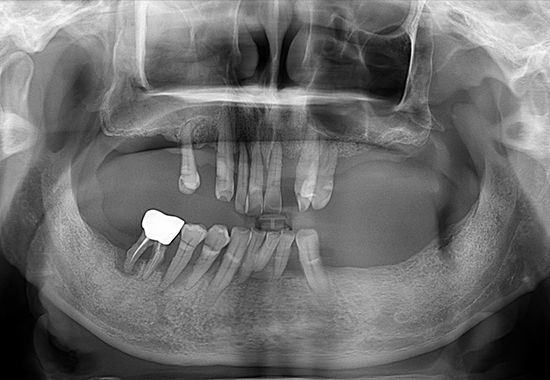

BEFORE

AFTER

- 식립 개수 : 15개 (상악7개 하악 8개)

- 수술 내용 : 상악동거강술, 치조골 이식, 자연치 신경치료